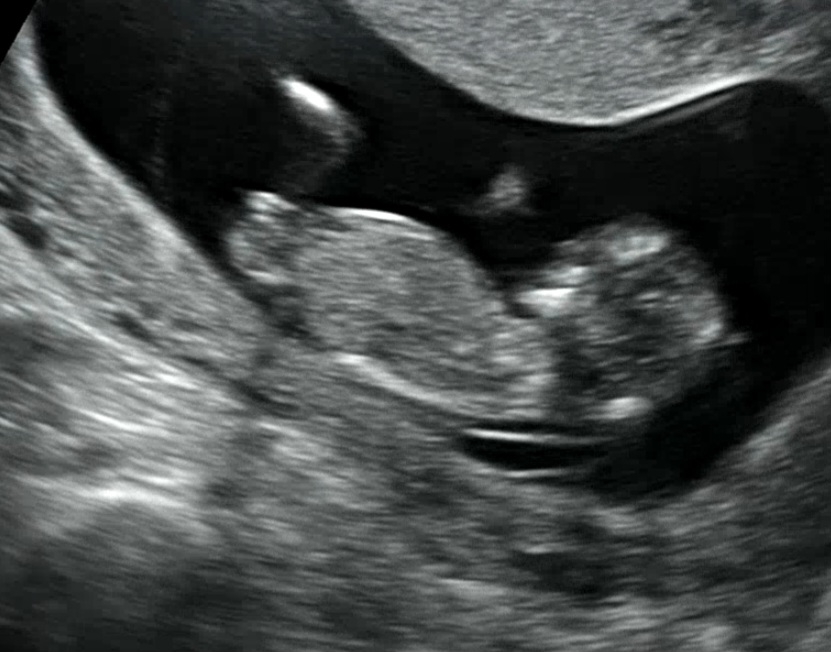

12주입니당 제가 보기엔 딸같은데.... 맞나요~?😮

각도법 궁금해용🤔

저두 딸같아요!

같은 띠용이네요😄 딸 기다리는데 감사해용!!